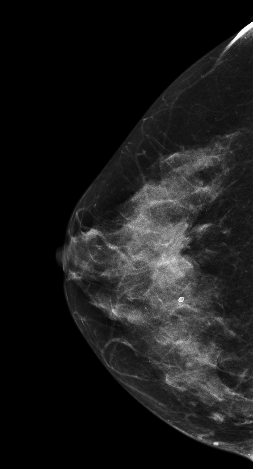

DBT图像:

在常规2DMLO位图像上象限见一较大分叶状肿块影,但在CC位上没有发现明显肿块影像,在V-Preview(合成2D)图像上乳头后方似见不规则密度区,但仍不能明确病变位置,在DBT-plane我们可以乳晕后方清晰见一分叶状肿块影,肿块边缘呈放射状毛刺样改变,亦可见粗大血管影,可以明确肿块大小范围。

影像诊断:

右乳上象限肿块,考虑恶性,BI-RADS 5级。

右乳浸润性癌。